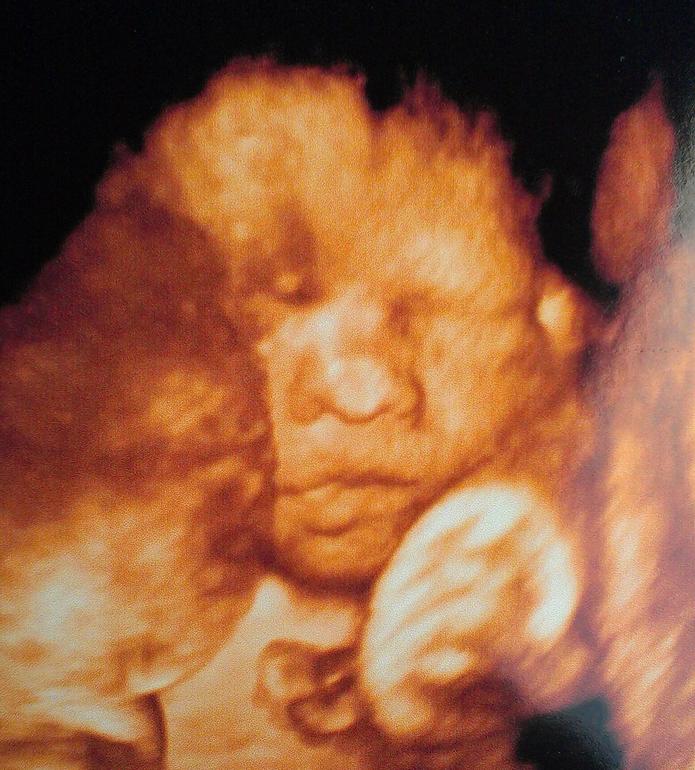

Срок по узи на 2 дня больше, чем по М. Предв.вес 880 гр. Большой мальчик, уже 25,6 нед. :) Пришли на узи, а наш мальчик спит, уткнувшись носом в плаценту, фото личика не сделать. Пришлось тормошить его минут 10, потом подвинулся, пару раз пнул, позевал и снова уснул )))) Но фото сделали к счастью. Похож на папу на этих фото. Фото под катом.